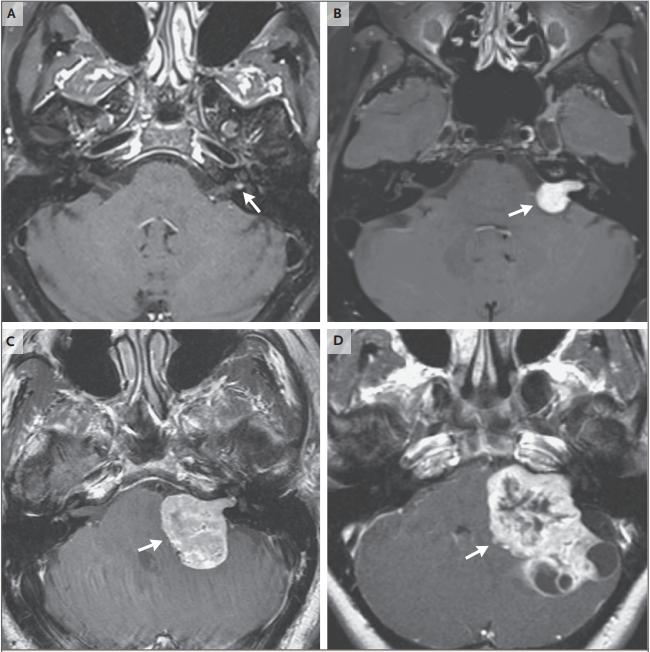

图2:诊断时前庭神经鞘瘤大小的变异

听神经瘤在注射增强对比剂前的T1加权 MRI序列显示为等信号,钆剂注射后呈强烈增强。根据大小不同,肿瘤可能完全局限于内耳道,也可能不同程度地延伸到桥小脑角。图A到图D分别显示轴向增强T1加权 MRI上左侧小、中、大和巨大(箭头)的前庭神经鞘瘤。随着肿瘤的生长,它会在内耳道范围内扩张,并对邻近神经施加压力,然后向中间方向生长到桥小脑角。较大的肿瘤延伸至桥小脑角可压迫位于头侧的三叉神经、尾侧的后组颅神经、脑干和小脑内侧。进展性脑桥中间抹平可能导致第四脑室梗阻和随后的脑积水。